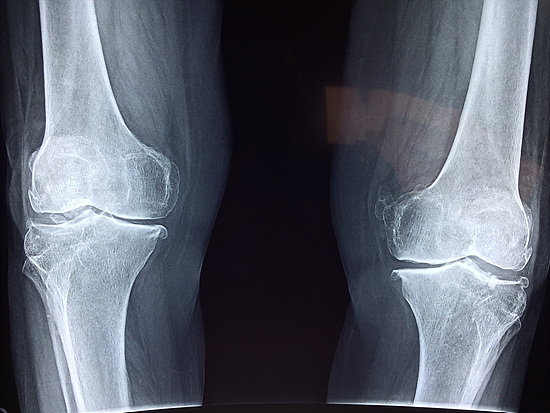

노화로 인해 퇴행하는 무릎 관절을 인공 관절로 교체하는 수술을 말합니다.

마모되거나 손상된 관절을 인공적인 재료로 만든 것으로 대체하여, 무릎의 기능을 회복시키고 통증을 줄여주는 의료 시술입니다.

이 수술은 관절염이나 그 외 다른 질환으로 인한 심한 통증과 기능 장애를 겪고 있는 분들에게 적극적으로 권장되고 있답니다.

노인분들에게 있어서는 일상생활의 활동 범위를 넓히고, 삶의 질을 향상하는 데 큰 도움이 되죠.